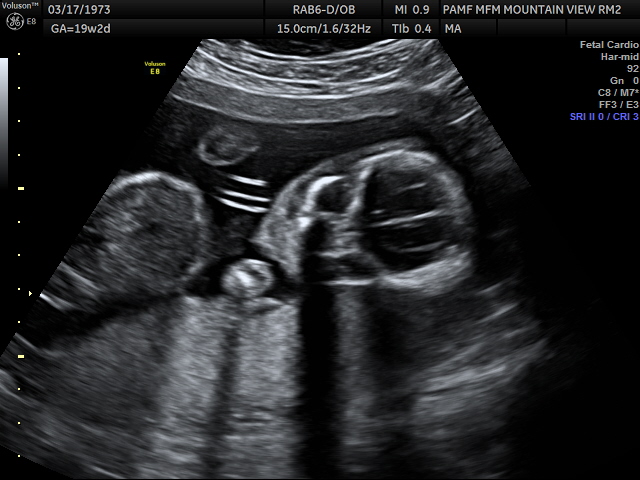

Other close ups were easier to make out like this head picture. It was fun seeing many parts and angles of our child in utero.